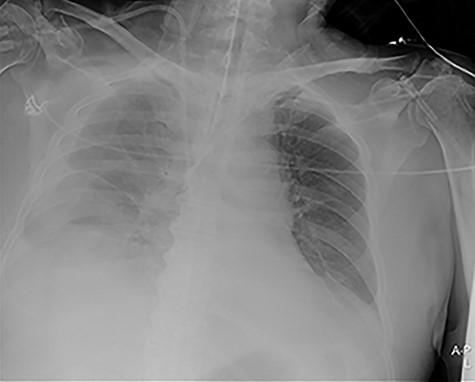

Our surgical team was contacted after 4 h, as the pleural fluid had become grossly haemorrhagic. A CXR showed haemothorax (Fig. 2). Upon clinical deterioration, the patient was intubated, and a 24Ch chest tube was introduced. Approximately, 500 ml of blood was immediately drained, followed by 300 ml during the first 30 min. ICA laceration was suspected. Despite transfusion of red blood cells and plasma and infusion of noradrenaline, the patient remained circulatory unstable. A new CXR showed massive haemothorax despite drainage (Fig. 3). The patient was now utterly haemodynamically unstable and not suited for transportation. As there are no thoracic surgeons or interventional radiologists in our hospital, the general surgeons decided to take him to the operating theatre. A wide anterolateral right thoracotomy was performed with patient lying in left lateral decubitus position. The right pleural cavity was full of fresh and coagulated blood. The pulsating bleeding was seen coming from the posterolateral, caudal chest wall, but the exact site deep down in the sharp costophrenic angle could not be localized and was inaccessible for any surgical haemostatic manoeuvre.

Portable chest X-ray in half-upright position showing haemothorax 4 h after placement of pigtail pleural drain.